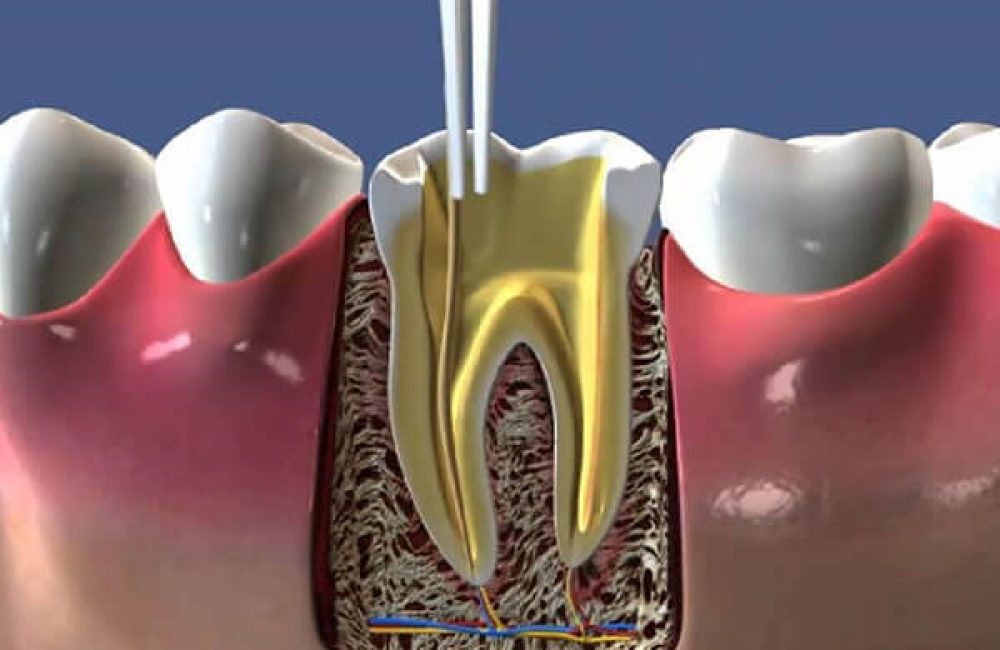

Uzman diş hekimi ya da endodontist tarafından yapılabilen kanal tedavisinde ilk adım röntgen çekimidir. Röntgen aracılığıyla diş kökünün içindeki kanalların durumu ve çevre dokularda enfeksiyon olup olmadığı görüntülenir. Buna göre uzman hekim tarafından dişe uygulanacak kanal tedavisi planlanır.

İkinci aşamada anestezi devreye girer. Kanal tedavisi lokal anestezi eşliğinde gerçekleştirilen bir tedavi yöntemidir. Anestezi aracılığıyla dişin yanındaki bölge uyuşturulur.

Üçüncü adımda diş içine bir kavite (delik) açılır. Söz konusu boşluktan girilerek sorunlu pulpa bölgesi, çürümüş haldeki sinir dokusu ve enfeksiyonlu partiküller çıkarılır. Dişin içi tamamen temizlenerek dezenfekte edilir.

Dördüncü aşamada doldurma işlemi gerçekleştirilir. Pulpayı ve diş sinirini çıkarmak amacıyla diş kökünde açılan boşluk özel bir kauçuk bileşeni kullanılarak doldurulur. İnsan vücuduyla uyumlu, herhangi bir alerjik reaksiyona yol açmayan guta perka isimli bu maddeyle doldurulan boşluk sayesinde olası enfeksiyonların önüne geçilmesi amaçlanır. Bu aşamanın sonunda kanal tedavisi de tamamlanmış olur.